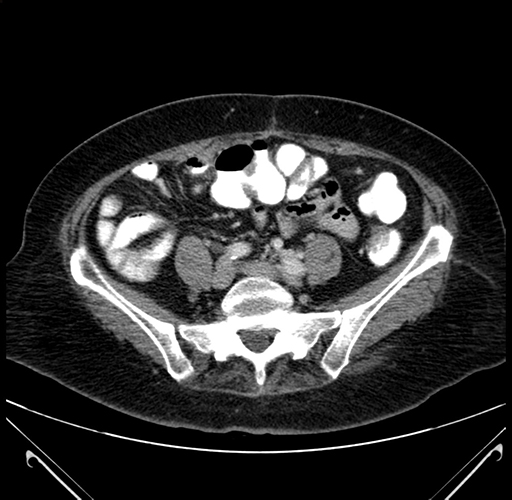

Pre-Chemo: Axial Venous

Imaging analysis

Based on your CT findings, which issue(s) would give reason for "planned slowing down moment(s)" in this case?

Considering a standard right hepatectomy procedure, what step(s) of the operation would you do differently in this case?